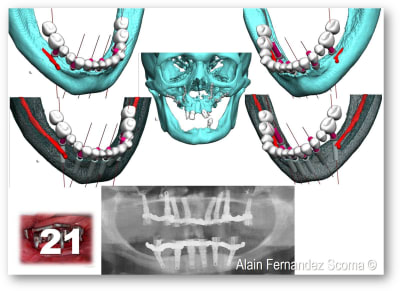

Comme tu peux l'observer sur l'image (21) malgré la complexité du cas il y a une recherche de symétrie contrairement à ce cas traité avec un guide à étage